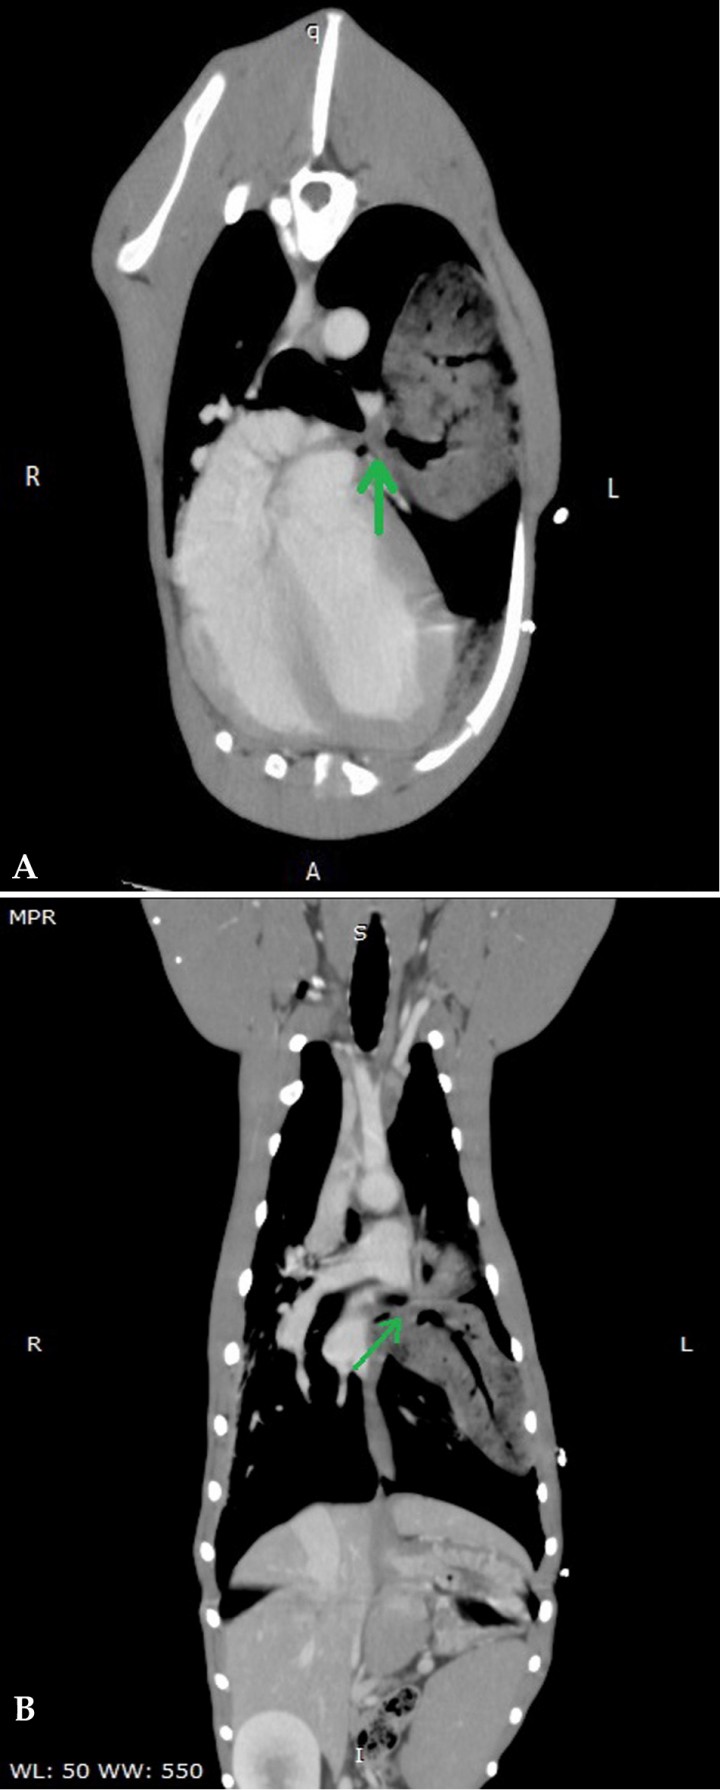

En las proyecciones lateral derecha (Fig. 2A) y ventrodorsal (Fig. 2B) se observa un patrón broncointersticial difuso, así como aumento de la opacidad en el aspecto craneoventral del tórax y leve retracción de lóbulos pulmonares craneales, compatible con efusión pleural moderada y atelectasia pulmonar secundaria. En la proyección ventrodorsal la efusión es menos evidente. En la proyección lateral, en la zona media del tórax existe un aumento de la opacidad uniforme a nivel del aspecto caudal del lóbulo craneal izquierdo, correspondiente con un signo lobar. Dicha lesión presenta broncogramas aéreos (patrón alveolar), con el extremo apical del lóbulo dirigido cranealmente. Esta misma imagen se observa en la proyección ventrodorsal, donde la porción caudal del lóbulo craneal izquierdo aparece desplazada caudalmente con respecto a su localización anatómica habitual, con aumento de la opacidad difusa y superposición con el lado izquierdo de la silueta cardiaca. En la proyección lateral, a nivel ventral y entre la cuarta y quinta costilla, se aprecian bronquios dilatados en áreas periféricas, que podría indicar bronquiectasias que no se visualizan en la proyección ventrodorsal.

<p>Mismas radiografías que la Fig. 1. (<strong>A</strong>) Nótese en la zona craneoventral del tórax (puntas de flechas verdes) un aumento de opacidad, compatible con efusión pleural. Posibles bronquiectasias (flecha verde) en la zona ventral entre la 4ª y la 5ª costilla. Retracción de los lóbulos pulmonares con aumento de opacidad y presencia de broncograma aéreo (flechas rojas) en la zona de la porción caudal del lóbulo craneal izquierdo (señalada con flechas verdes en la Fig. 2B). (<strong>B</strong>) Desplazamiento caudal del lóbulo craneal izquierdo respecto a su zona de proyección anatómica, con aumento de opacidad y superposición parcial con el lado izquierdo del corazón (flechas verdes).</p>

Mismas radiografías que la Fig. 1. (A) Nótese en la zona craneoventral del tórax (puntas de flechas verdes) un aumento de opacidad, compatible con efusión pleural. Posibles bronquiectasias (flecha verde) en la zona ventral entre la 4ª y la 5ª costilla. Retracción de los lóbulos pulmonares con aumento de opacidad y presencia de broncograma aéreo (flechas rojas) en la zona de la porción caudal del lóbulo craneal izquierdo (señalada con flechas verdes en la Fig. 2B). (B) Desplazamiento caudal del lóbulo craneal izquierdo respecto a su zona de proyección anatómica, con aumento de opacidad y superposición parcial con el lado izquierdo del corazón (flechas verdes).

La colocación del drenaje torácico favorece la resolución del derrame pleural, persistiendo el signo lobar (broncogramas aéreos) que afecta al aspecto caudal del lóbulo craneal izquierdo y el desplazamiento de la zona apical hacia craneal.